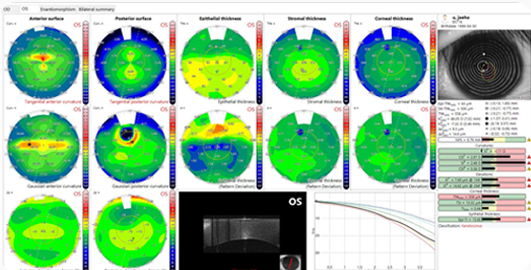

퍼펙트 올레이저수술을 완성하는 MS-39